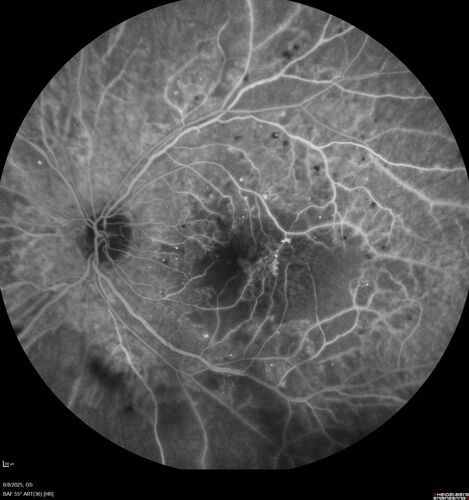

NPDR and Severe macular ischemia sudden vision loss

60 year old female with sudden vision loss OD 1 week ago. VA 20/63, 20/200. OCT-A and FA shows severe macular ischemia OU